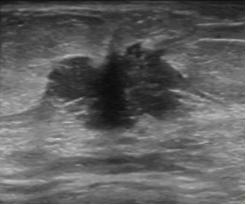

3.乳腺结节的边缘。

分为:光整和不光整(模糊、成角、微小分叶、毛刺等)。边缘光整是指:结节的边缘与周围组织界限清晰,往往是良性结节的特征。结节边缘不光整往往是乳腺癌的征象,指的是:模糊(结节的部分边缘无清晰的边界)、微小分叶(结节边缘出现锯齿状结构)、成角(结节边缘部分或全部形成锋利的角度,通常为锐角)、毛刺(从结节的边缘放射状的锋利细线)。

结节边缘为微小分叶,术后病理为恶性